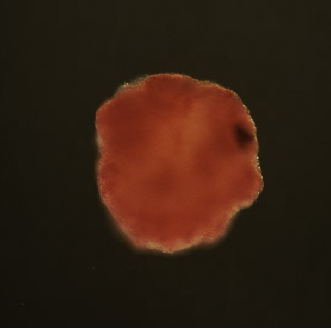

荧光染色证实胰岛类器官包含原生胰岛组织所有成熟的功能细胞,比例均衡、分部合理,与原生胰岛近似。

自发分化形成人胰岛类器官,减少了人为干预,提高了生产效率,降低了成本;保留了所有细胞间连接和通讯,确保细胞间自我调控和胰岛素分泌功能正常。